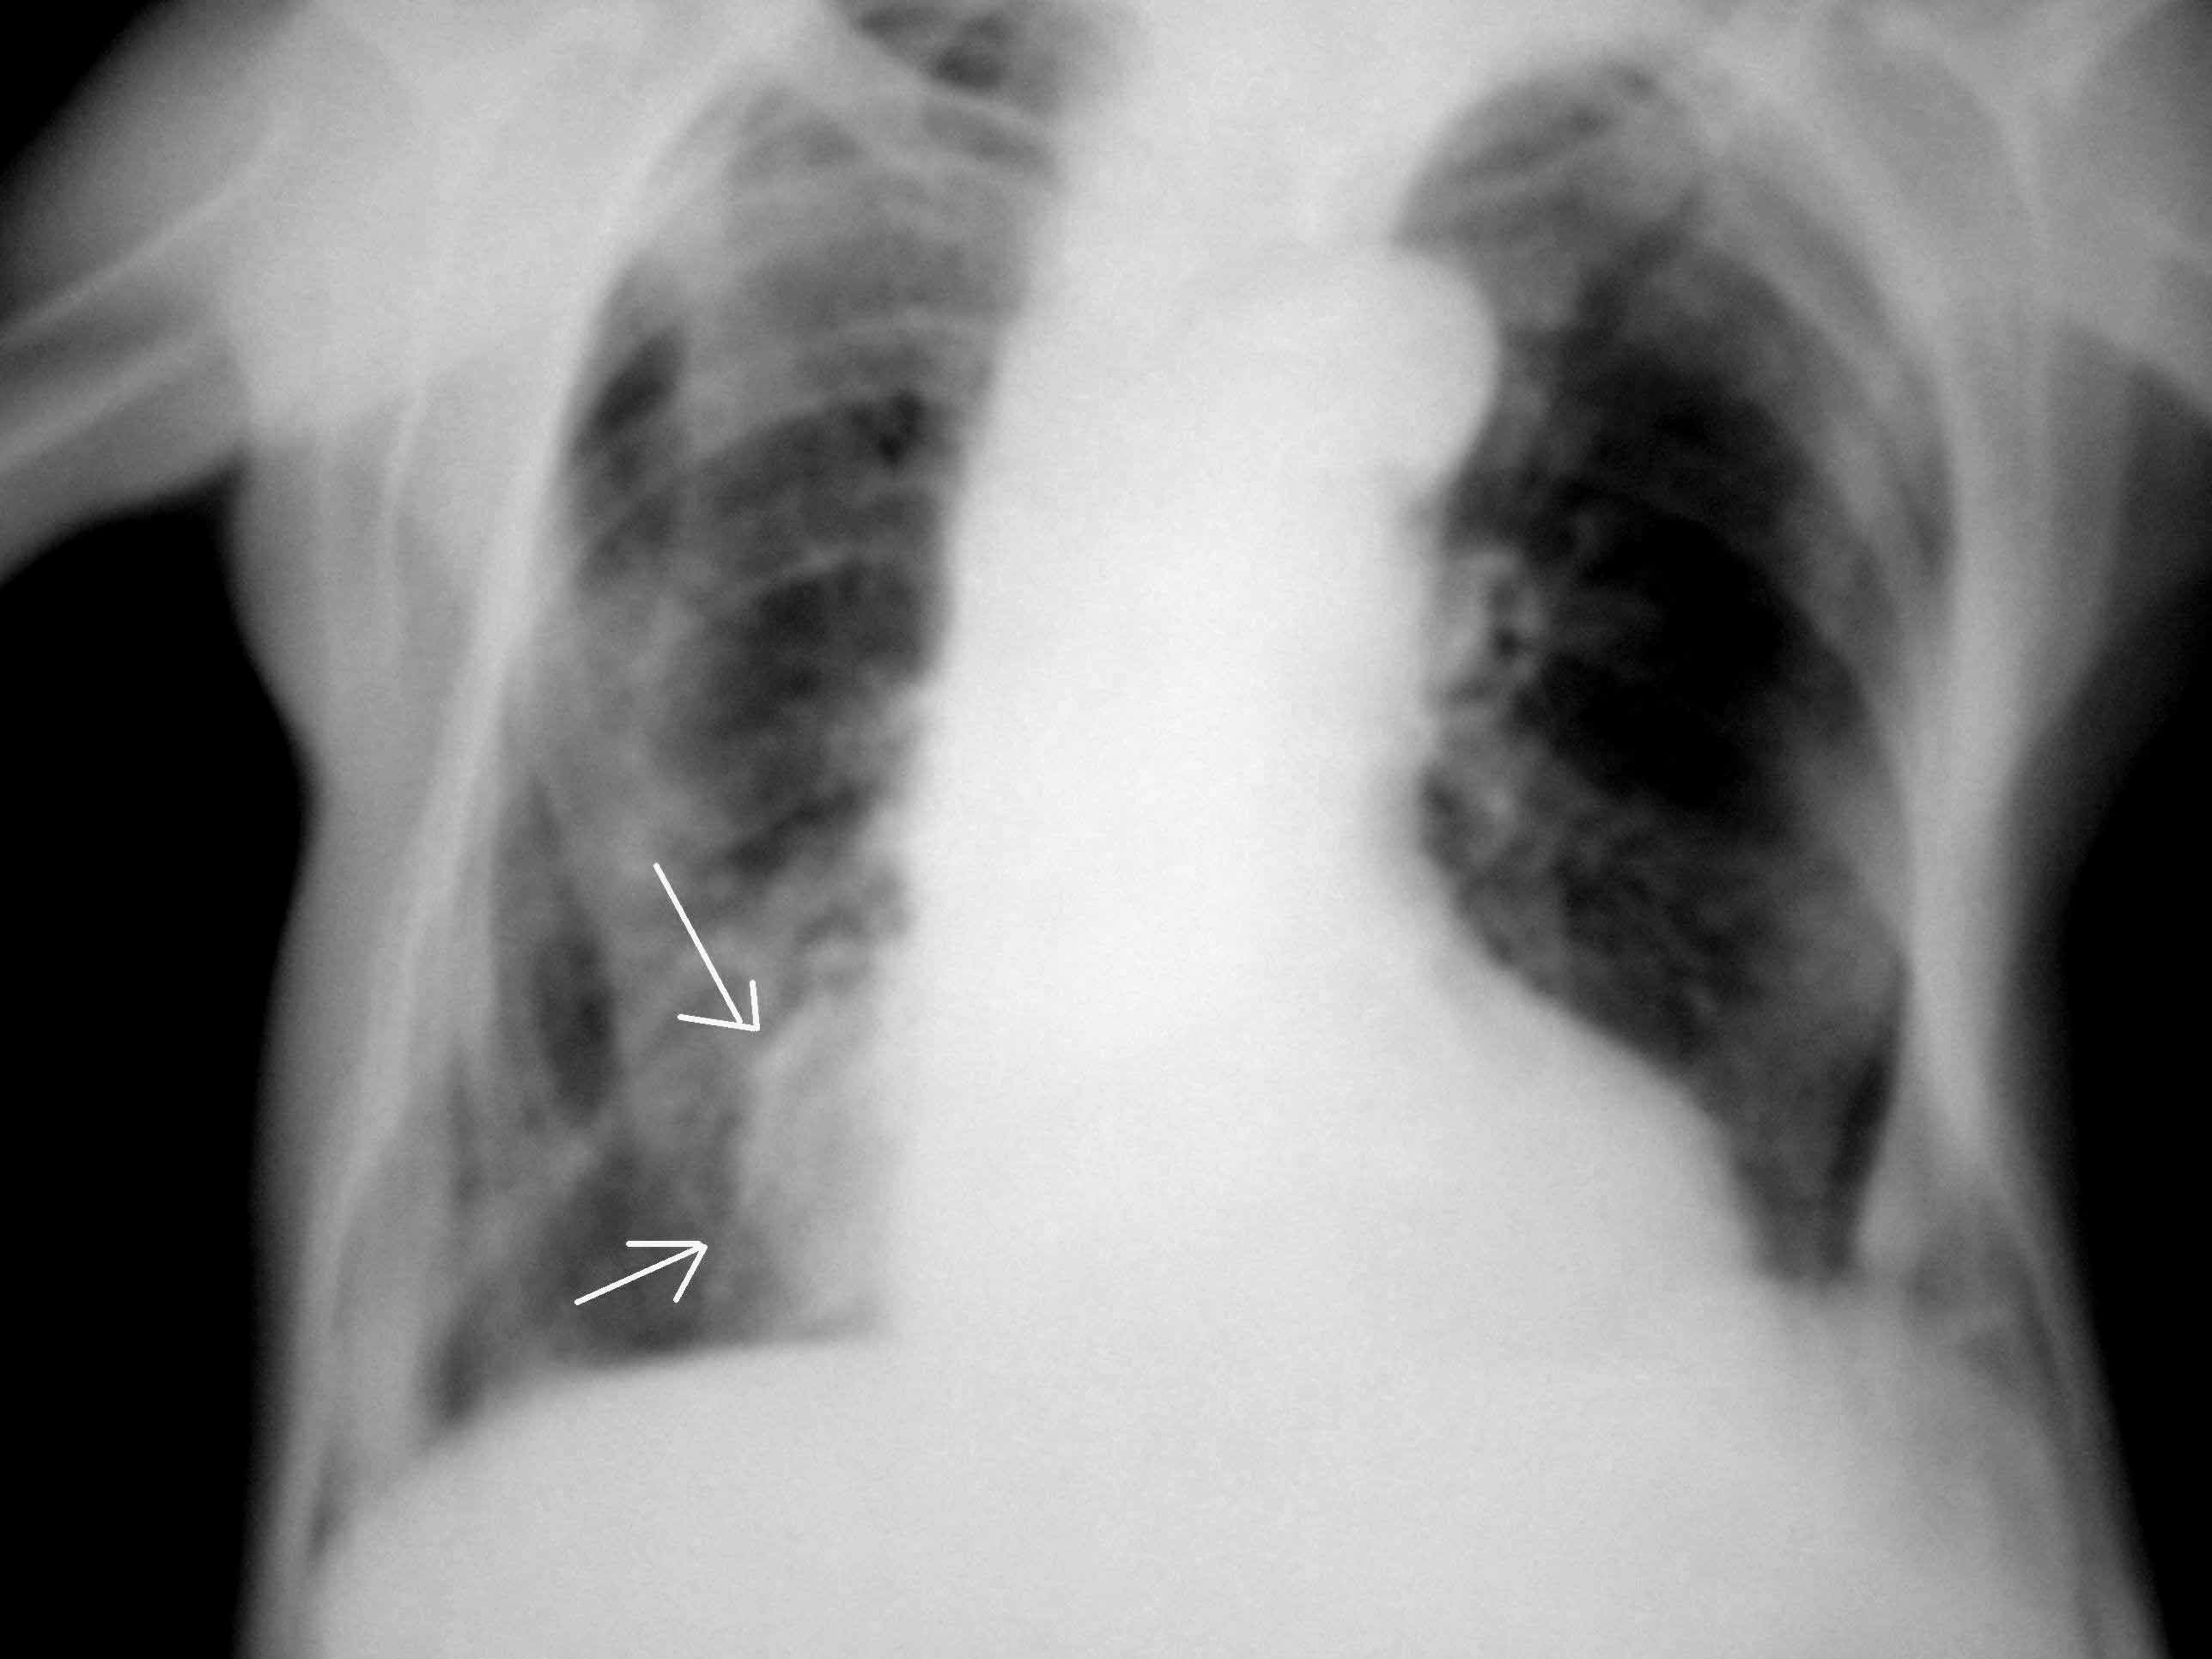

男,60岁,胸痛一周。箭头所示是右心还是异常影?是病变的话会是什么?透视机坏了观察不了搏动情况,我建议病人加照侧位但还没过来照。请各位帮忙看看,谢谢。

右下肺野的病灶(和/或纵隔)

此病人胸廓有畸形,不考虑病变,

可能为降主动脉延长迂曲所致。

脊柱侧弯。建议加照侧位或ct进一步检查。

像病灶影:局限性肺不张?球形肺炎?

考虑病灶!!其形态不太符合右心缘!